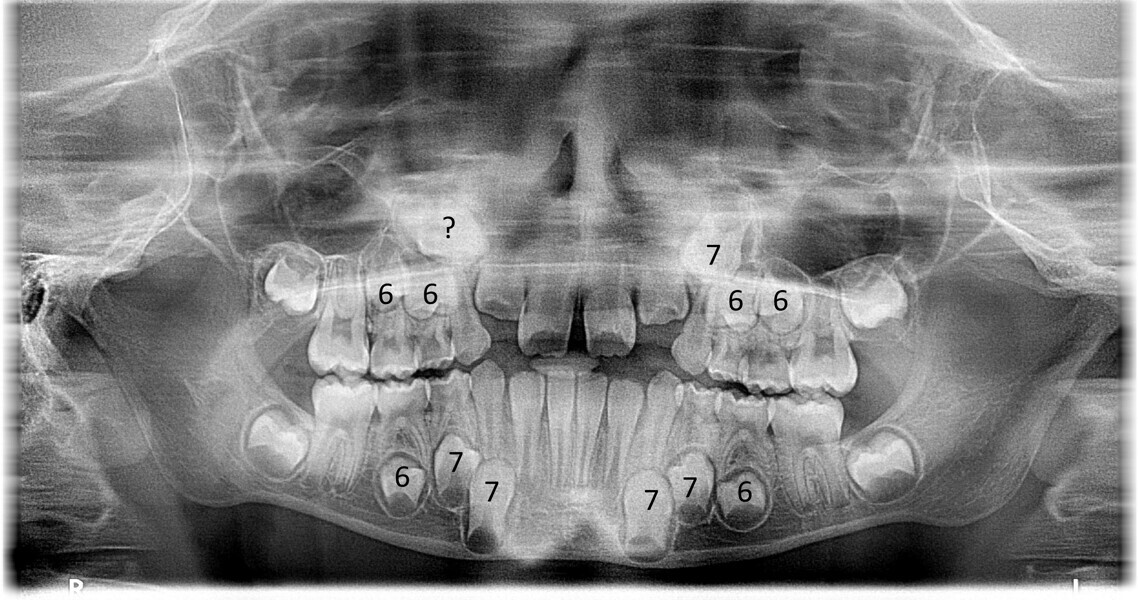

The dental panoramic tomograms showed early mixed dentition and Nolla indices of permanent canines and premolars of between 6 and 7 (Fig. 3).22 This was an optimal indication for aligners because excellent stability of the posterior sectors was guaranteed, which we believe is essential for achieving effective dentoalveolar movements even in the case of arch expansion and good support to align the anterior sectors of the arches.